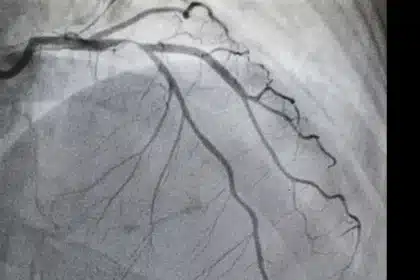

A groundbreaking algorithm identifies moderate-to-severe aortic stenosis (AS) with 90.5% sensitivity across patients and 100% accuracy in African American individuals. This tool offers hope for earlier detection in underserved groups…

A groundbreaking algorithm identifies moderate-to-severe aortic stenosis (AS) with 90.5% sensitivity across…